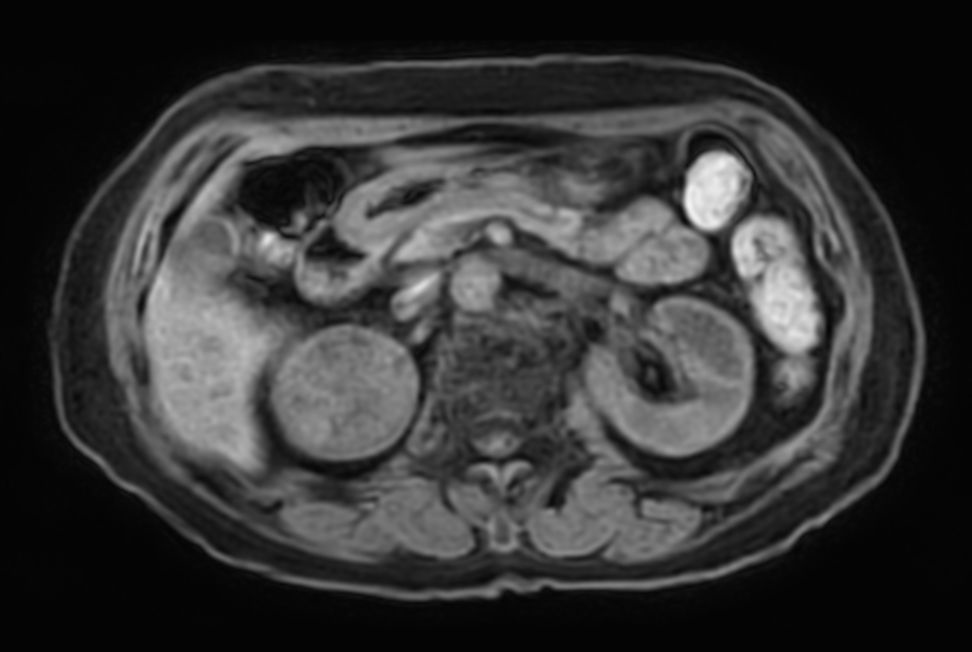

Patient with renal failure. ExamCard includes MultiVane XD to acquire motion-free diagnostic images and 4D FreeBreathing to perform multi-phase contrast-enhanced MRI studies.

T2w TSE - Free Breathing